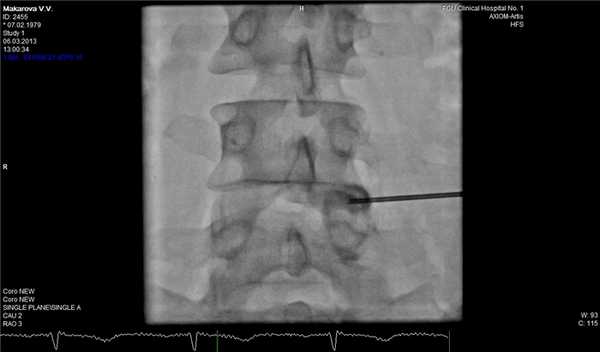

Фораминальная рецидивная грыжа 5 мм. Дискография.

Сдавление корешка L4 в корешковом канале, несмотря на малые размеры грыжи. Эпидурография.